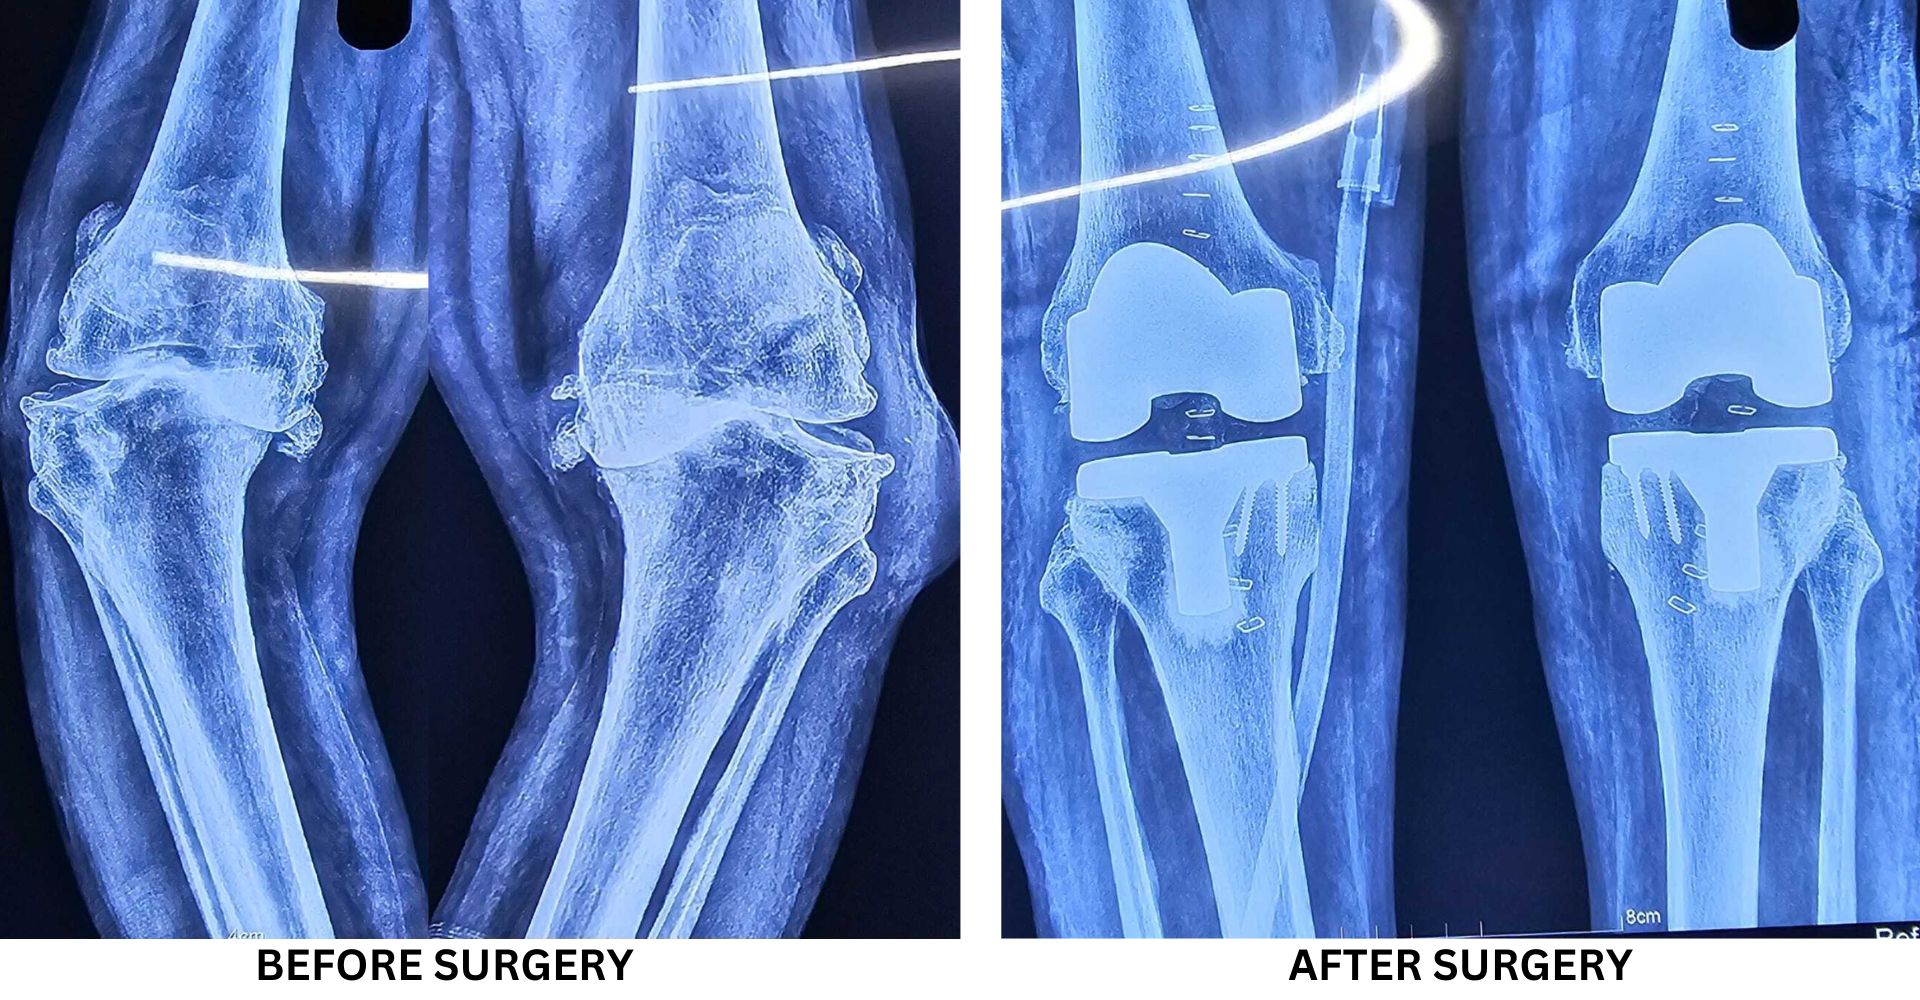

Gallery